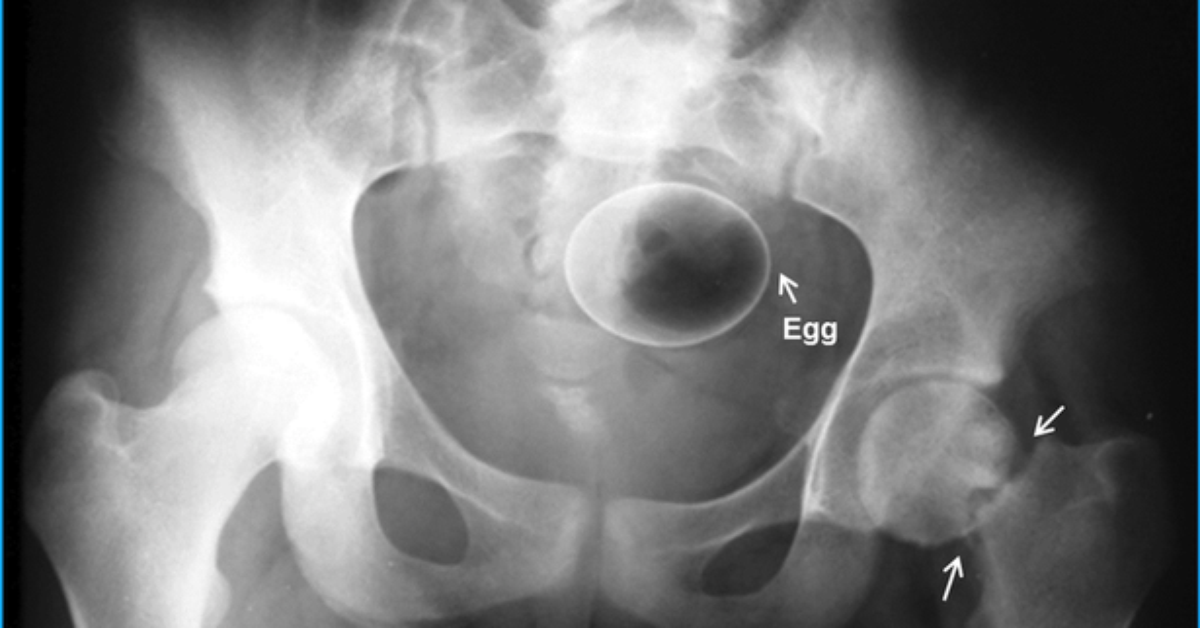

De Ovo A Garrafa Veja Objetos Bizarros Achados Em Raios X